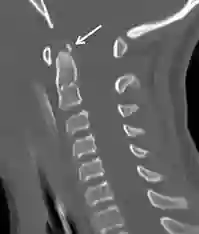

A persistent terminal bone fragment can be optimally visualized in imaging with a sagittal CT imaging of the cervical spine.

Ossiculum terminale CT

Sagittal CT imaging of a patient with a terminal ossicle (white arrow). Figure adapted from DOI: 10.1007/s00381-016-3199-7